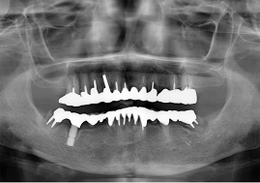

短いインプラント(ショートインプラント)を使用し、骨造成を行わないグラフト術式。